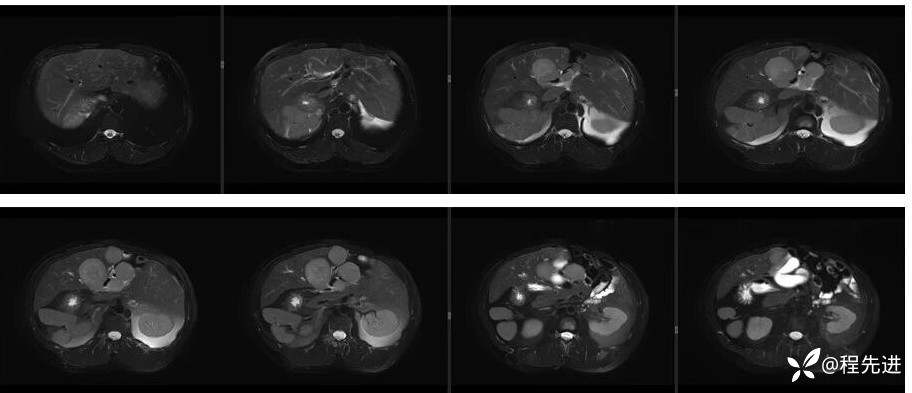

辅助检查:上腹部平扫+增强扫描提示:肝脏、脾脏、胰腺 、胃十二指肠左右倒置,脾脏形态失常,呈分叶团块状,考虑发育变异。肝左右交界区多发肿块,考虑:上皮样血管内皮瘤可能性大,或转移瘤?其它?请结合临床。脂肪肝。肝门胆管局限性扩张。胆囊折叠,壁稍增厚,慢性炎症?胰腺下方椭圆形结节,副脾?

影像检查